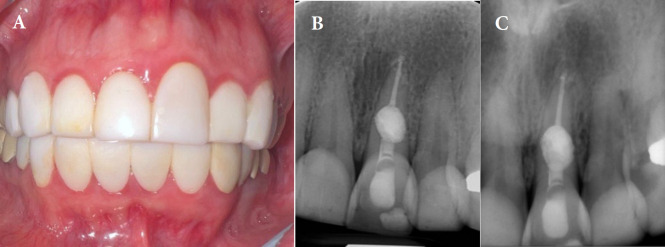

Internal inflammatory root resorption (IRR) poses significant challenges in endodontic treatment due to its potential to compromise tooth integrity. This case report describes the conservative management of IRR in a 40-year-old woman with a radiolucent lesion in the midroot of a maxillary central incisor. Early diagnosis using cone-beam computed tomography prevented perforation and guided treatment planning. Non-surgical endodontic treatment was performed using a dental operating microscope, ultrasonic irrigation, and a hybrid obturation technique. The apical portion of the canal was sealed with a bioceramic sealer and single-cone gutta-percha, while the resorptive defect was filled with calcium-enriched mixture cement due to its biocompatibility and sealing properties. At one-year follow-up, the patient was asymptomatic, with radiographic evidence of healing. This case highlights the efficacy of combining advanced diagnostic tools, bioactive materials, and minimally invasive techniques for successful IRR management.